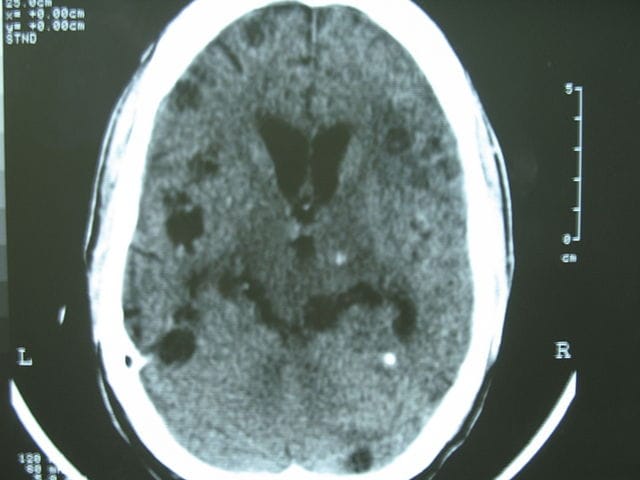

- Görüntüleme: Manyetik Rezonans Görüntüleme (MRI) ve Ultrason (USG), kas içindeki kistlerin varlığını ve iltihaplanma derecesini gösteren en etkili araçlardır. USG’de kistin içindeki parazitin başının (skoleks) görülmesi kesin tanıya yardımcı olur.